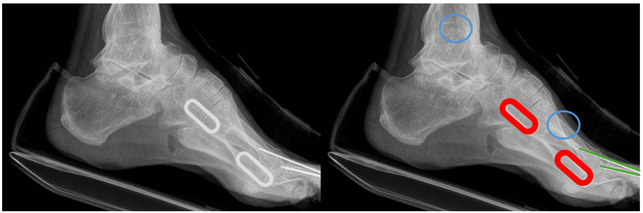

발(Foot): 1st, 2nd metatarsal bone 등 8개 영역의 세그멘테이션과 1번째 발등뼈 관절면 끝을 지정하는 4개의 키포인트, 종자골(sesamoid bone) 영역의 바운딩 박스를 라벨링했습니다.

기존에 전문의가 족부 X-ray 100명 기준으로 4개 지표를 수작업 추출할 때 4주(40시간)가 걸리던 작업을, AI 모델 적용으로 단 2시간으로 줄이는 것을 목표로 합니다.